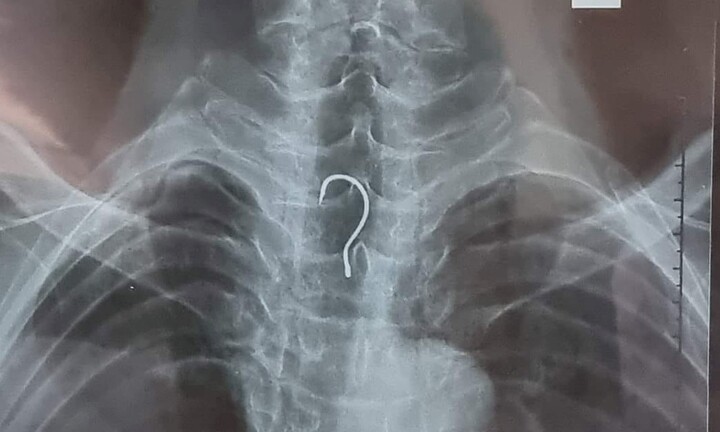

Cụ ông 83 tuổi mắc lưỡi câu trong bụng

Bệnh viện Đa khoa tỉnh Hà Tĩnh vừa thực hiện nội soi, gắp ra ngoài chiếc lưỡi câu dài 4cm trong thực quản của một cụ ông.